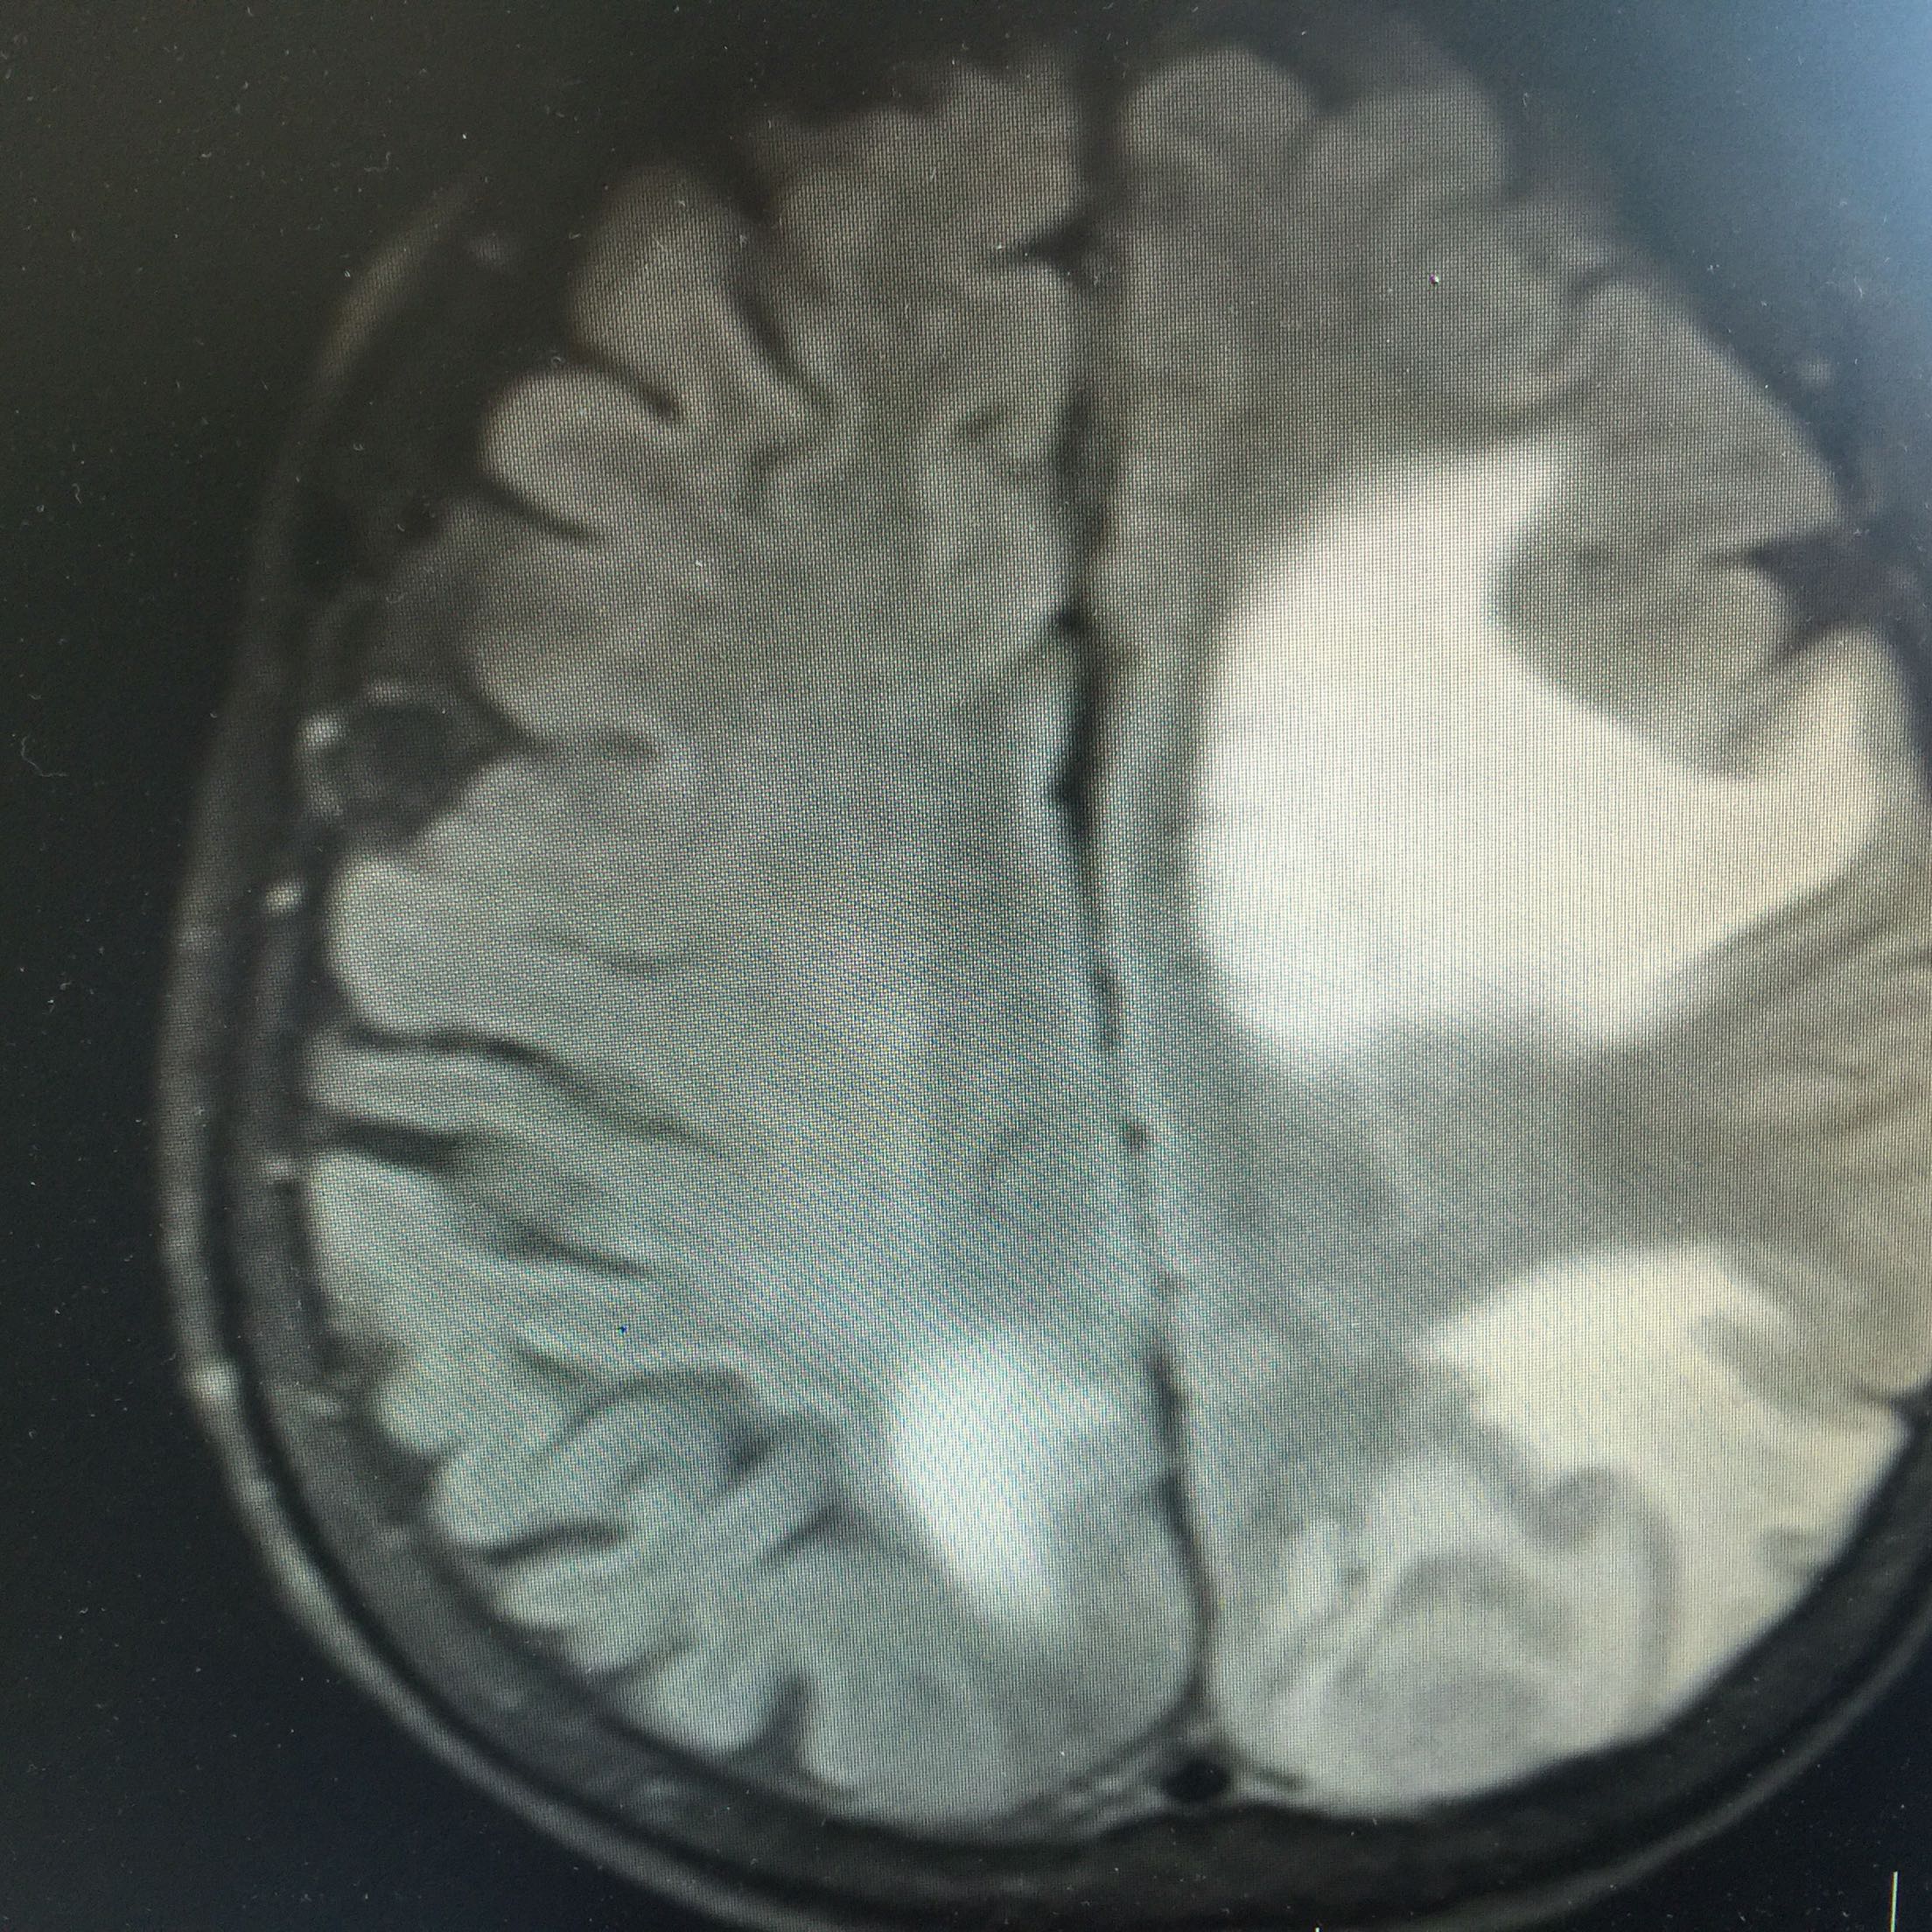

1.女,81岁,以“右侧肢体无力3天”入院。 2.现病史:3天前无诱因出现右侧肢体无力,右上肢抬举费力,右下肢步行拖拉,无抽搐,无意识障碍! 3.既往史:2016年肺穿刺活检,免疫组化为腺癌!已合并第五、六椎体转移、左肾上腺转移,行灌注介入治疗。

查体:血压:130/80mmHg,两肺呼吸音清,未闻及啰音,心率98次/分,律齐,未及杂音,双下肢无水肿。神经系统查体:意识清,双侧瞳孔等大正圆,直径约3.0mm,对光反射灵敏,无面舌瘫,右侧肢体肌力4级,腱反射减弱,Babinski征R+L-。

左肺腺癌 骨转移、双肺门及纵膈淋巴结转移、左肾上腺转移、脑转移! 治疗:对称、支持治疗!